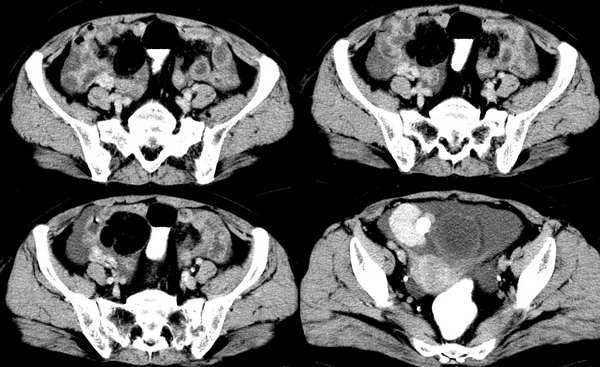

女,59岁,憋气、下腹不适一个月。胸透:双侧大量胸腔积液,反复抽胸水化验为漏出液。彩超示:盆腔占位

膀胱右前方类圆形软组织占位,边界光整,增强后明显强化,与口服造影剂密度相当,随后密度减低,强化均匀,考虑盆腔右侧血管源性占位。

麦格综合症(卵巢纤维瘤并胸水)。

支持麦格综合症(卵巢纤维瘤并胸水)。生殖器官恶性肿瘤待排